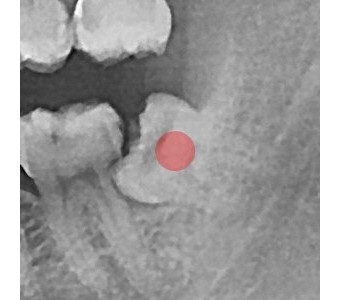

결과로 증명합니다.

국제모아치과의

실제 임상 증례